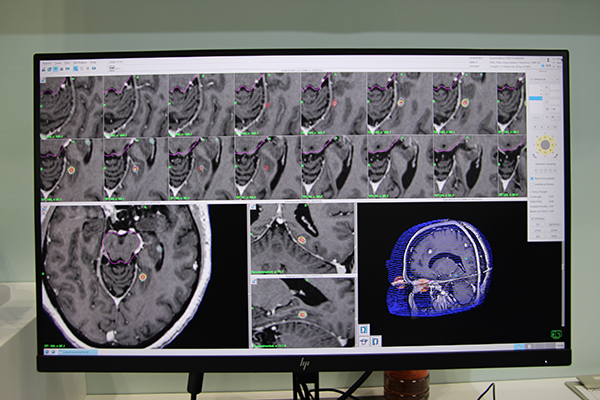

ニューロサイエンス分野では,頭部専用の定位放射線治療機器ガンマナイフの最新モデル「Leksell Gamma Knife Icon(アイコン)」の治療計画装置「GammaPlan Ver11.1」が初出展された。Iconは,ガンマナイフとしては初めてマスクシステムが採用された装置で,Real Time HD Motion Managementシステムにより,照射中の体動を赤外線でリアルタイムにモニタリングすることで,従来の照射精度を保証しつつ,幅広い症例への対応が可能になった。今回展示されたGammaPlan Ver11.1は,Icon専用の治療計画装置で,ブースでは,実際の治療計画作成やCBCT撮影後の治療計画の補正,Icon装置へのデータの送信などのフローが,モニタを用いて紹介された。

治療計画装置「GammaPlan Ver11.1」のデモ画面